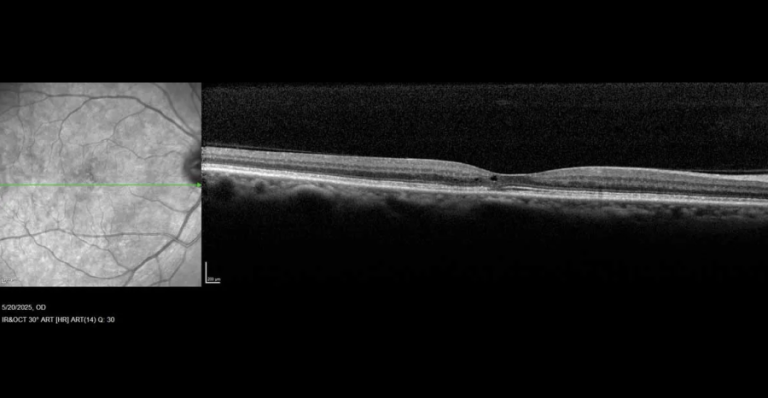

Ilustración conclusión del articulo: En la figura A se ilustra la coroides bastante

conservada en la forma CSC inducida por esteroides. En la figura B se representa la

coroides de la CSC idiopática con mayor dilatación de los vasos y mayor grosor de

esta capa de grandes vasos.